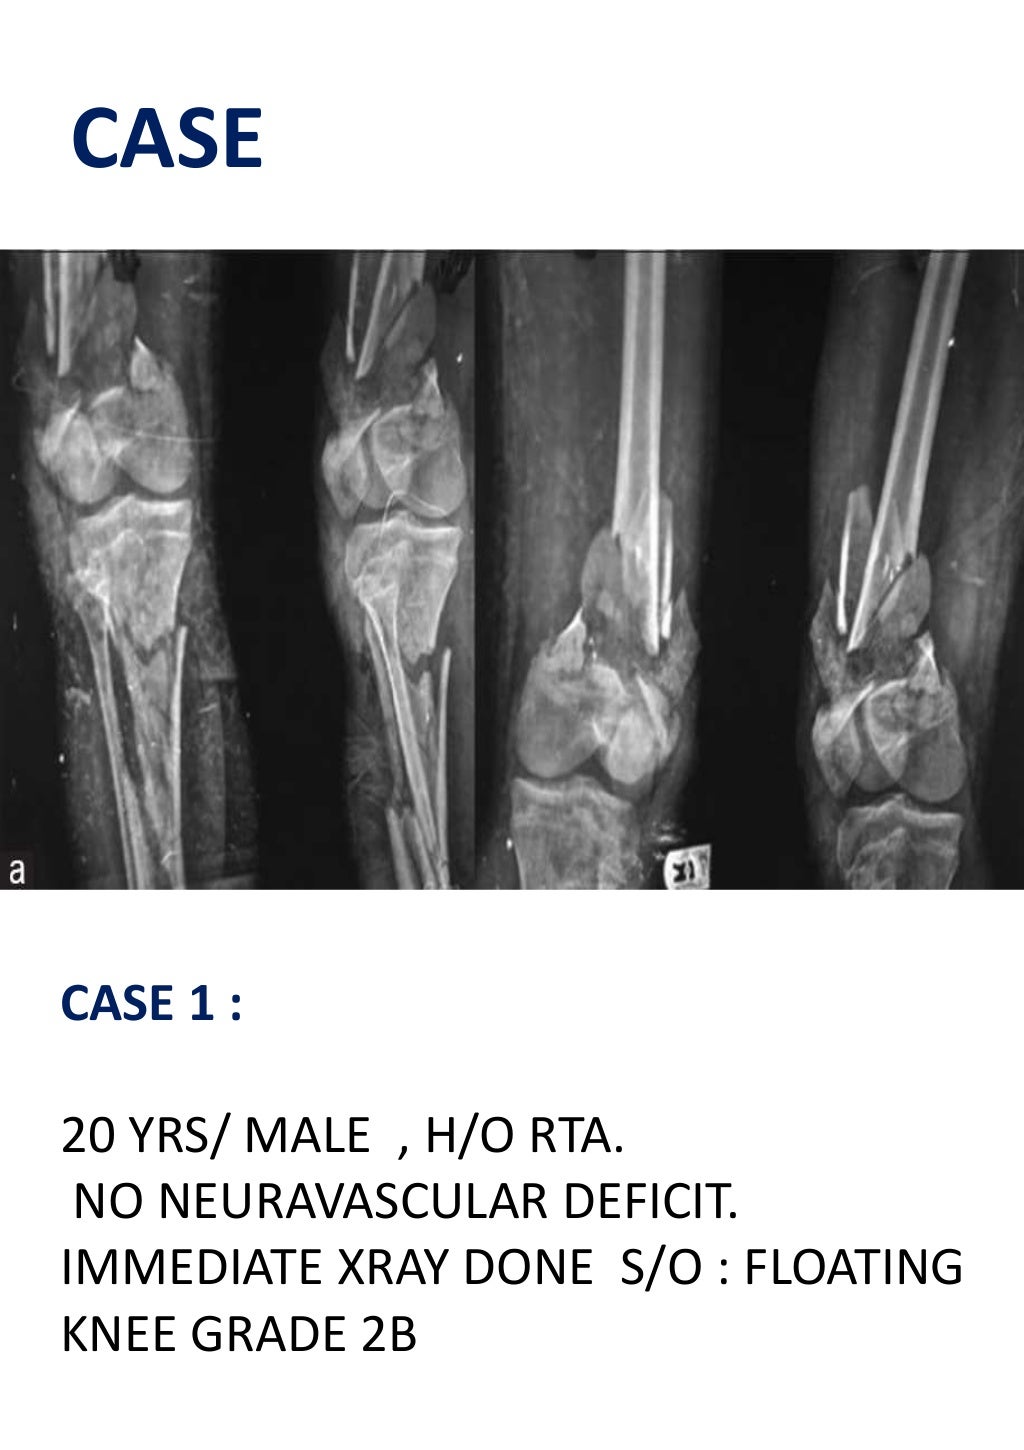

The floating knee epidemiology, prognostic indicators &

Floating knee A modified Fraser's classification and the results of a Floating Pieces In Knee Everyone has cartilage in their knees, but there could be an injury that requires. A loose body is essentially a fragment of cartilage or bone that has broken away from the surface of the knee joint. If you feel something strange in your knee joint — like something's floating in there — it may be articular cartilage. These fragments can. Floating Pieces In Knee.

Floating knee A modified Fraser's classification and the results of a Floating Pieces In Knee Loose bodies are another name for free floating pieces of debris in the joint. They are tissues that have torn away from their original location and. Knowing how to identify a loose body in your knee can help you seek out the right support when you’re struggling with a persistent pain. They can be the result of an injury or. Floating Pieces In Knee.

Floating knee A modified Fraser's classification and the results of a Floating Pieces In Knee When these fragments get trapped between the articular. Knowing how to identify a loose body in your knee can help you seek out the right support when you’re struggling with a persistent pain. They can be the result of an injury or from generalized wear. In more severe cases, these symptoms can. Loose bodies are fragments of cartilage or bone. Floating Pieces In Knee.